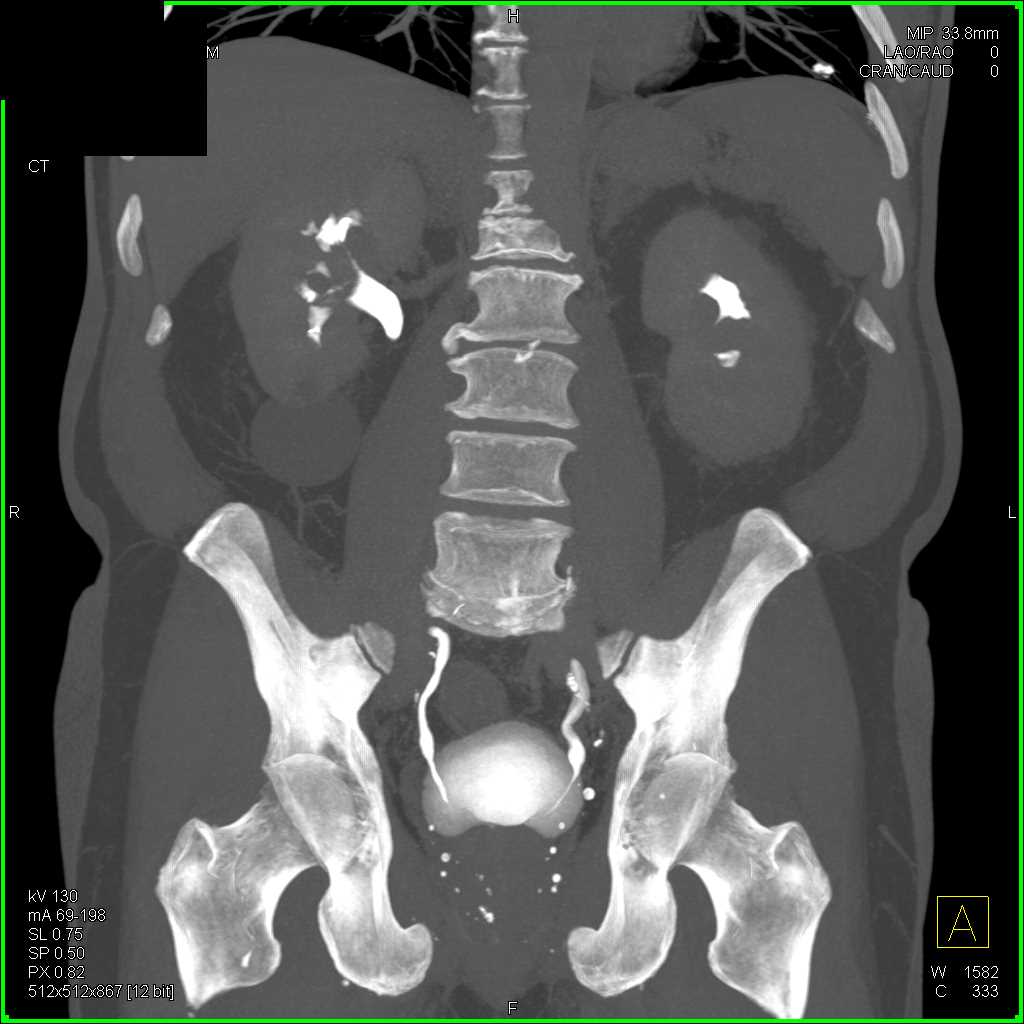

Acute Pyelonephritis Right Kidney